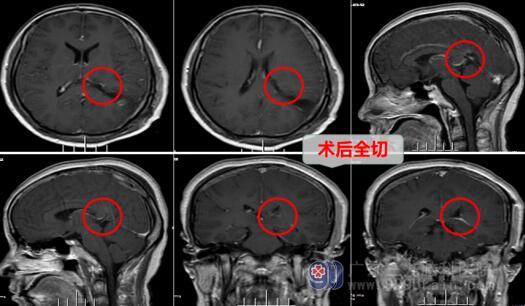

欧阳辉主任听完尹女士的描述,立即为她安排了磁共振,查看病变及周围神经组织等的情况。从MR结果分析,欧阳辉主任考虑占位病变为脑室内脑膜瘤的可能较大。家属一听十分紧张,想着脑袋长出肿瘤,是多么可怕的一件事,欧阳主任解释道:脑膜瘤并非可怕,绝大多数脑膜瘤属于良性肿瘤,根据肿瘤发生的位置不同,可出现不同的临床症状,不必过于担心。及时治疗,才是关键!

家属听完欧阳辉主任解释后立即办理了入院手续,第二天完善检查后,在针对尹女士病情,神经外十科做出了一套治疗方案,家属签完手术同意书,由欧阳辉主任主刀,带领医生团队为尹女士在全麻下行内镜辅助下左侧脑室三角区肿瘤切除术。手术非常成功,尹女士当天恢复清醒,随后送往神经外十科住院病房继续康复治疗。